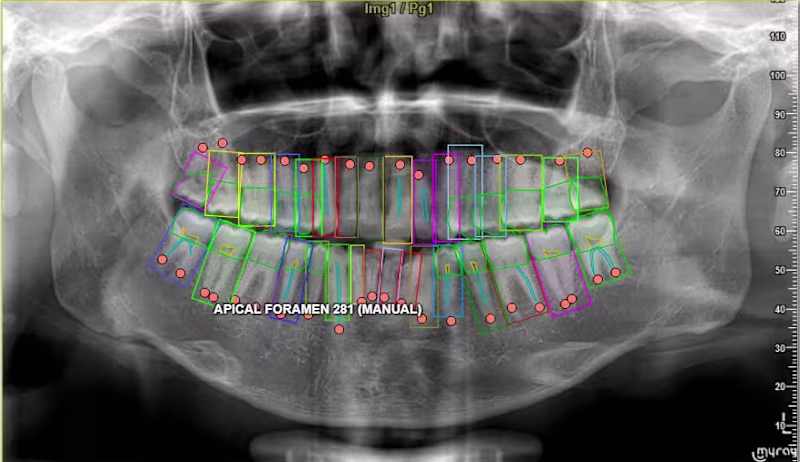

Annotated complex dental X-ray medical imaging datasets used to train AI models for healthcare applications. The project involved precise labeling of anatomical structures including teeth boundaries, roots, and surrounding regions using polygon and keypoint annotation techniques. The objective was to generate high-quality training datasets that allow machine learning systems to accurately detect dental structures and support medical imaging analysis. Responsibilities included: • Image segmentation and polygon annotation • Keypoint labeling for anatomical structures • Dataset preparation for machine learning models • Annotation quality control and validation This work contributes to the development of AI systems used in medical diagnostics and healthcare imaging analysis.